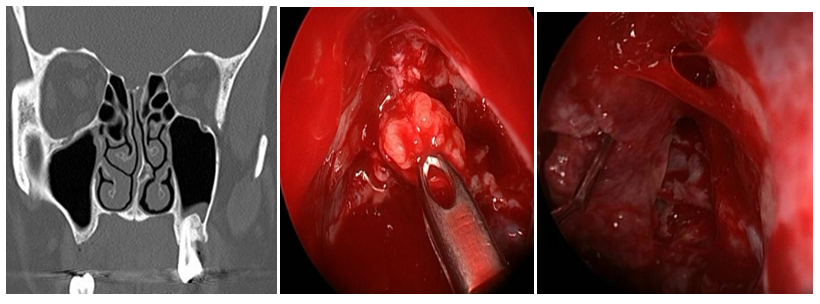

Intranasal MC was the most frequent lesion (6/5) and there was one patient with MEC (1/6). Five cases were idiopathic and one patient had history of transnasal surgery for a tumor of the sellar region and sphenoid plane 15 days before. 83,3% of the cases were primary surgeries and one patient had 3 prior MC surgeries. In 2 cases the MC was located in the sphenoid lateral wall (Figures 1A-B), one was located in the sphenoid roof (Figure 2), 2 in the cribriform plate and one patient, with MEC diagnosis, had it located in the frontal sinus. 66,6% had anterior rhinorrhoea (4/6) (Table 1). All patients were studied before surgery, only in four of them (66,6%) the lesion location was detected by at least one of the studies (CT, MRI and/or endoscopy). For one patient with MC of the lateral sphenoid wall intrathecal fluorescein was used prior to surgery (10cc of CSF were extracted by lumbar puncture and mixed with 0.2ml of 5% fluorescein, then 1ml per minute was delivered by intrathecal injection. We performed a multilayer closure technique in all patients (Figures 3A-C). In 4 cases we used autologous fat with mucoperichondrium (Figures 4A-B) and (Figures 5A-C) and in 2 cases autologous cartilage with mucoperichondrium. We used an intranasal transpterygoid approach for one case of lateral sphenoid wall mucocele, a Draf III technique in une case of frontal sinus MEC (Figures 6A-E). During the immediate postoperative period, one patient had acute meningitis that resolved with intravenous empirical antibiotics. One patient had a CSF leak recurrence 4 months after surgery. He was treated by external approach and had no relapse. No complications during postoperative follow up. The success rate of the reconstructions performed by endonasal approach was 83.33% (5/6). The average follow-up of the patients was 15 months.

Figure 1A-B Lateral Sphenoid wall MC (Sternberg canal) Enhaced CT Scan and MRI.

Figures 3A-C Lateral Sphenoid wall MC, multilayer closure technique.